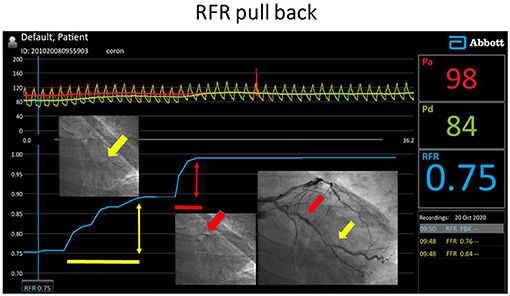

Figure 2

RFR pullback investigation in the left circumflex artery with intermediate stenoses. Both lesions proved to be significant according to the local ΔRFR.

The co-registration of the coronary angiography and the pressure pullback trace of the RFR measurement is based on the simultaneous fluoroscopic acquisition of the pressure wire position and the pressure trace. Using a reference image together to the pullback of the pressure wire under fluoroscopy can indicate quite precisely the beginning and the end of the lesion can be marked simultaneously on the Quantien equipment by the Marker function. The difference between the distal and the proximal value of the RFR markers will be used in the calculation of the ΔRFR (Figure 2).

If both the focal and diffuse criteria are fulfilled in the investigated vessel, then mixed type disease is diagnosed (Figure 2).